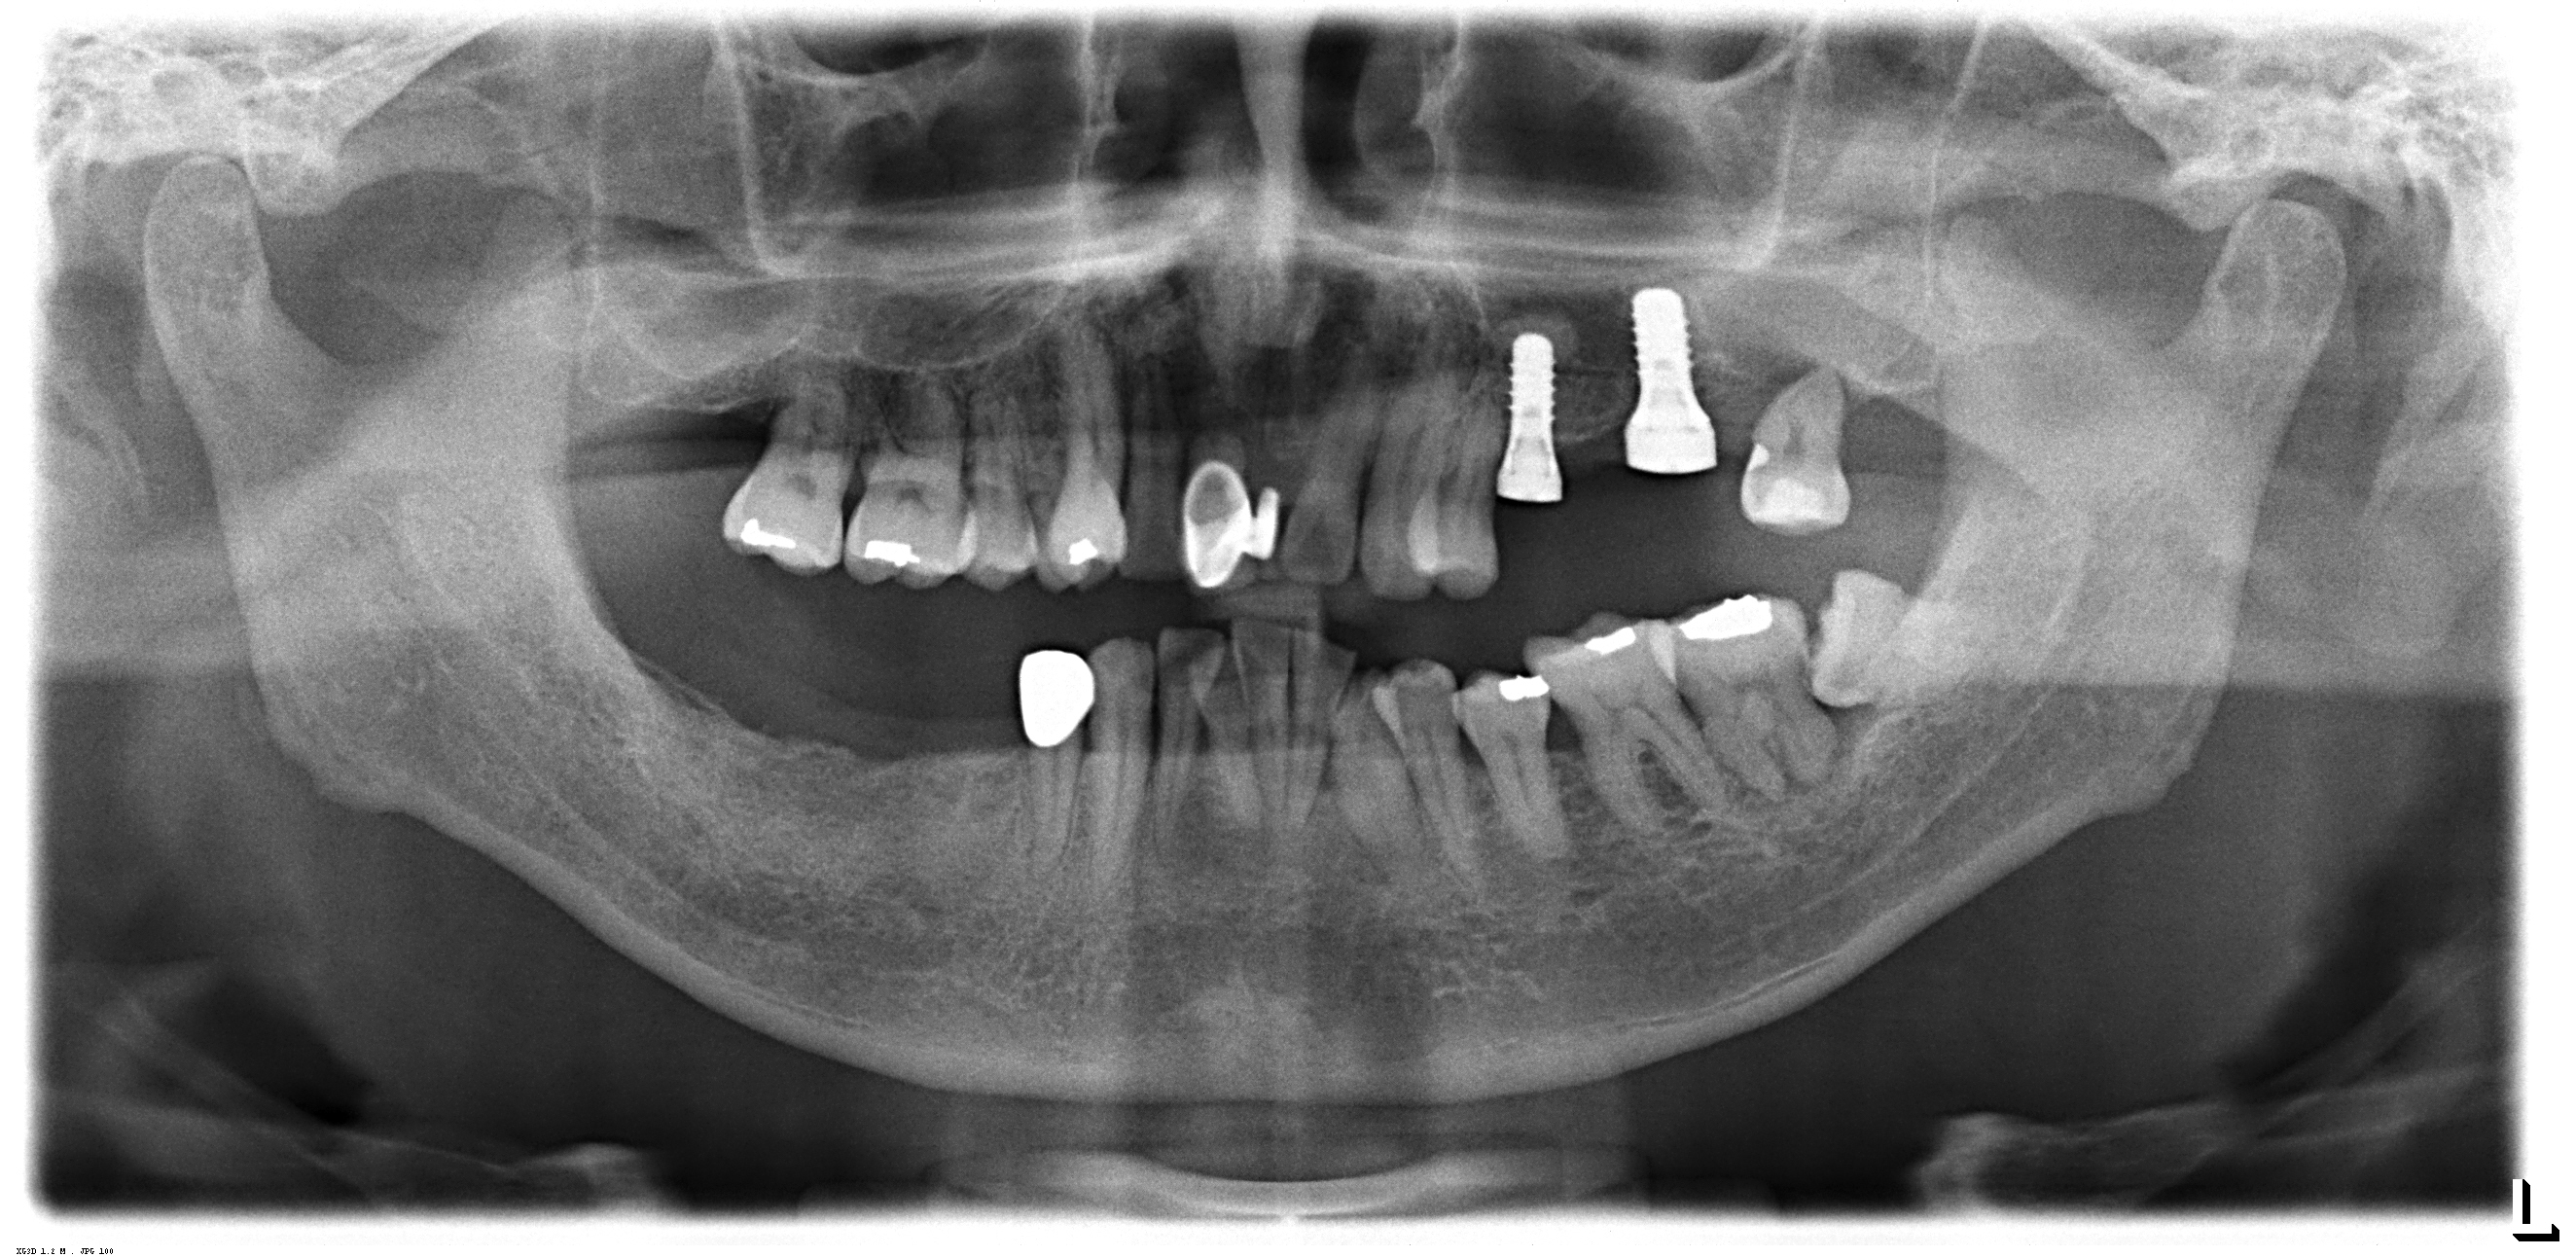

この患者さんは、歯周病のリスクが高いのでストローマンティッシュレベルインプラントを使用しました。

ティッシュレベルインプラントは、骨縁埋入型にインプラントのようにマイクロギャップ(インプラント体とアバットメントのつなぎ目)が無いため、インプラント周囲炎のリスクが少ないです。

このケースは、上顎5,7番部位へ2本のストローマンティッシュレベルインプラントをソケットリフトで埋入しました。